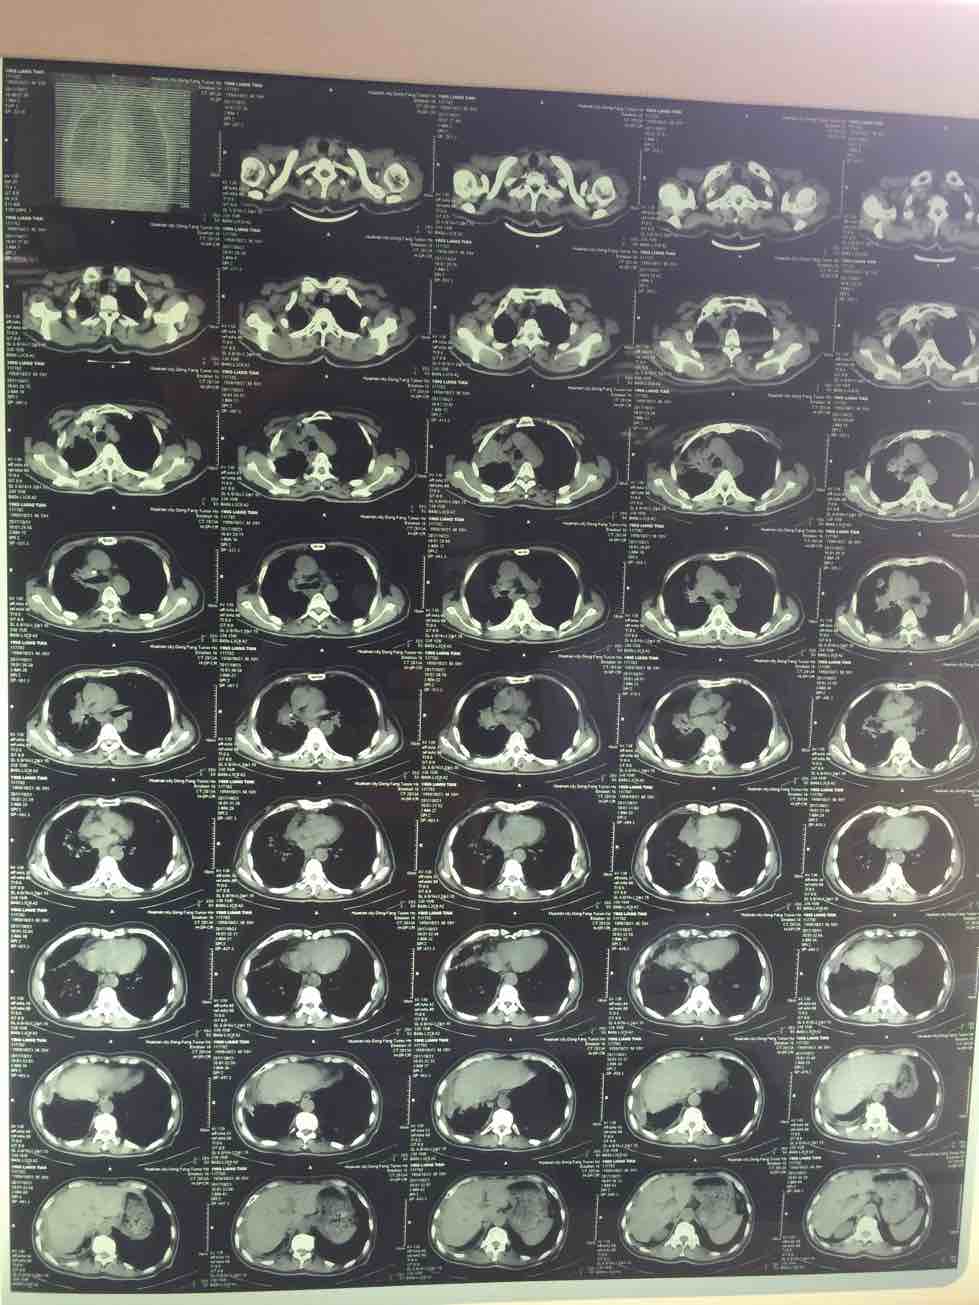

我父亲67岁,2016.1出现咳嗽不好,后进一步检查是肺腺癌晚期两肺广泛转移伴骨转移,吉西他滨 顺铂两次无效,培美曲塞加顺铂6次,效果很好最后耐药,基因检测9基因全阴性,后盲吃易瑞沙有效7.5盒进展了耐药,吃9291三盒半耐药,目前把培美曲塞拉回来单药做了一次,结果不理想,咳嗽喘憋加重,目前当地医生建议用恩度或阿帕替尼试试,请教各位老师是否有好的办法,谢谢